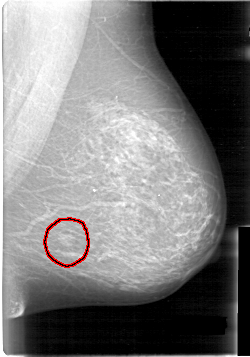

FILE: D_4014_1.LEFT_MLO.OVERLAY

TOTAL_ABNORMALITIES 1

ABNORMALITY 1

LESION_TYPE MASS SHAPE LOBULATED MARGINS OBSCURED

ASSESSMENT 0

SUBTLETY 5

PATHOLOGY BENIGN

TOTAL_OUTLINES 1

BOUNDARY